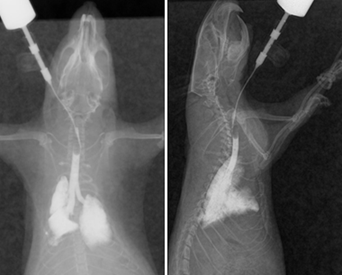

Культя рентген

Культя рентген 136 фотографий